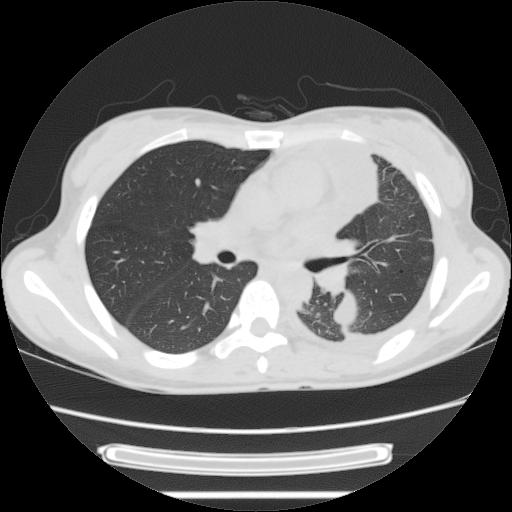

女,29岁,胸部不适,在外院胸片提示胸腔积液,到我院ct检查。

肺窗:

左侧纵隔胸膜包裹性积液、左侧胸腔积液、胸膜肥厚粘莲,考虑结核性胸膜炎

左肺上叶不张,左侧胸水,叶间裂积液,纵隔淋巴结,脾脏钙化,考虑左肺上叶支气管内膜结核,结核性胸膜炎,脾结核

左侧纵隔胸膜包裹性积液、左侧胸腔积液、胸膜肥厚粘莲,考虑结核性胸膜炎.左肺上叶支气管内膜结核,结核性胸膜炎,脾结核.

左肺上叶不张,左侧胸水,叶间裂积液,纵隔淋巴结,脾脏钙化,考虑左肺上叶支气管内膜结核,结核性胸膜炎,脾结核。支持!